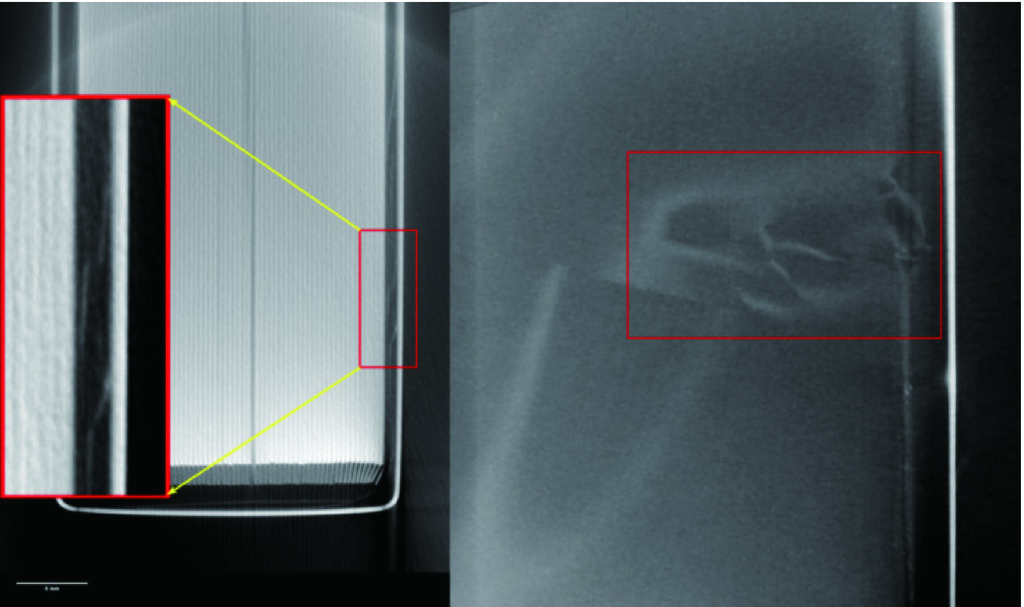

在本实验中,我们特别测量了代表标准肝脏密度(ρew=1.06)的插入物(图1箭头指示)。在整个扫描过程中,体模的位置始终保持固定不变。

使用一台256排CT(Revolution CT,GE医疗)完成体模扫描工作(图1)。在进行扫描时,参照腹部诊断CT扫描参数设置(表1),将管电压设定为120 kVp[15],并根据需要调整管电流,以产生6种不同的辐射剂量(容积CT剂量指数(volume CT dose index(CTDIvol):30、20、15、10、7.5和4.5 mGy)。其中,以15 mGy的剂量为标准的腹部扫描剂量[13]。重建图像的层厚和层距都是1.25 mm,重建图像视野为30 cm×30 cm,图像重建矩阵为512×512。